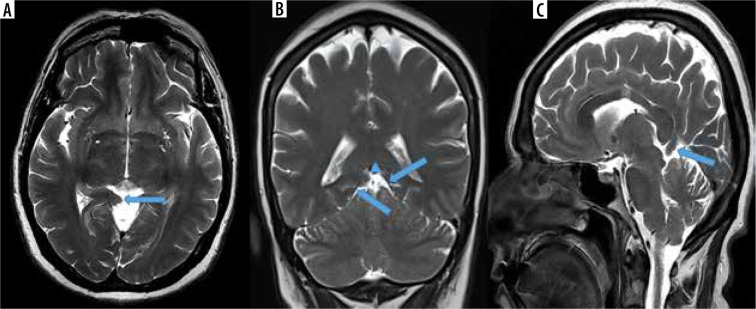

Purpose: The tent shape of the tentorium cerebelli helps preserve brain anatomy by providing cerebellum protection against pressure caused by the brain's gravity effect. In the absence of this support structure of the tentorium, herniation occurs in the brain. Isolated tentorial hypoplasia (TH) is extremely rare. In this study, we aimed to calculate the prevalence of this entity, which is reported to be rare in the literature.

Material and methods: Magnetic resonance imaging (MRI) images of 5163 patients who applied to the training and research hospital for various reasons between 1 September 2020, and 31 August 2021, who underwent brain MRI, were reviewed retrospectively.

Results: The prevalence of TH among patients screened during a period of one year was calculated as 2.22%. Of these, 76.59% were female (n = 72) and 23.41% were male (n = 22). The rates of presentation of complaints among TH patients were 60.63% headache, 17.02% vertigo, 4.25% seizures, 3.19% tremor, 3.19% syncope, 7.44% forgetfulness, and 2.12% visual impairment. Five patients (11.76%) were admitted for metastasis investigation due to their primary malignancy; they did not have any complaints. Localization of TH: 18.08% (n = 17) were observed on the right side, 28.72% (n = 27) on the left side, and 53.19% (n = 50) on the bilateral tentorium leaf.

Conclusions: Being aware of TH during brain MRI evaluation will help prevent possible misdiagnoses. We hope that this study with a large number of patients will increase awareness about TH, because there are no studies other than cadaver studies and a few case reports.